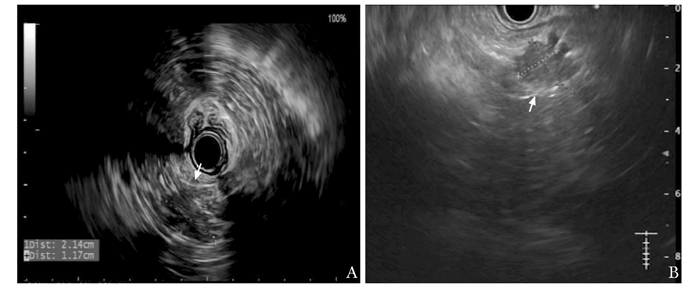

• 摘要: 一例老年男性患者因胰尾部胰岛素瘤反复发作导致低血糖,频繁发作意识障碍,因传统影像学的局限性难以具体定位肿瘤位置,且患者高龄伴慢性肾脏病,外科手术治疗风险较高。经多学科团队讨论后,采用前沿的影像学检查方法和新兴的内镜治疗技术,最终解决了患者的诊治难题。在该例患者诊治过程中,多学科团队应用本领域最新技术共同诊治,体现了多学科协作的重要性。

Abstract: This patient had recurrent hypoglycemia and frequent disturbance of consciousness caused by the insulinoma, but the definite location of the tumor could not be determined due to the limitations of conventional imaging, and he was unable to undergo surgical treatment because of his advanced age and chronic kidney disease. After multidisciplinary discussion, we applied cutting-edge imaging examination and emerging endoscopic treatment techniques, and finally solved the problem of diagnosis and treatment of the patient. This process reflects the importance of multidisciplinary cooperation: various disciplines explore the latest technologies and progress in the fields, and jointly assist in the management of complex diseases.